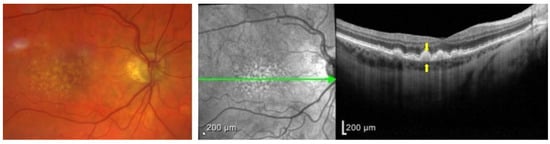

1.3. Clinical Presentation